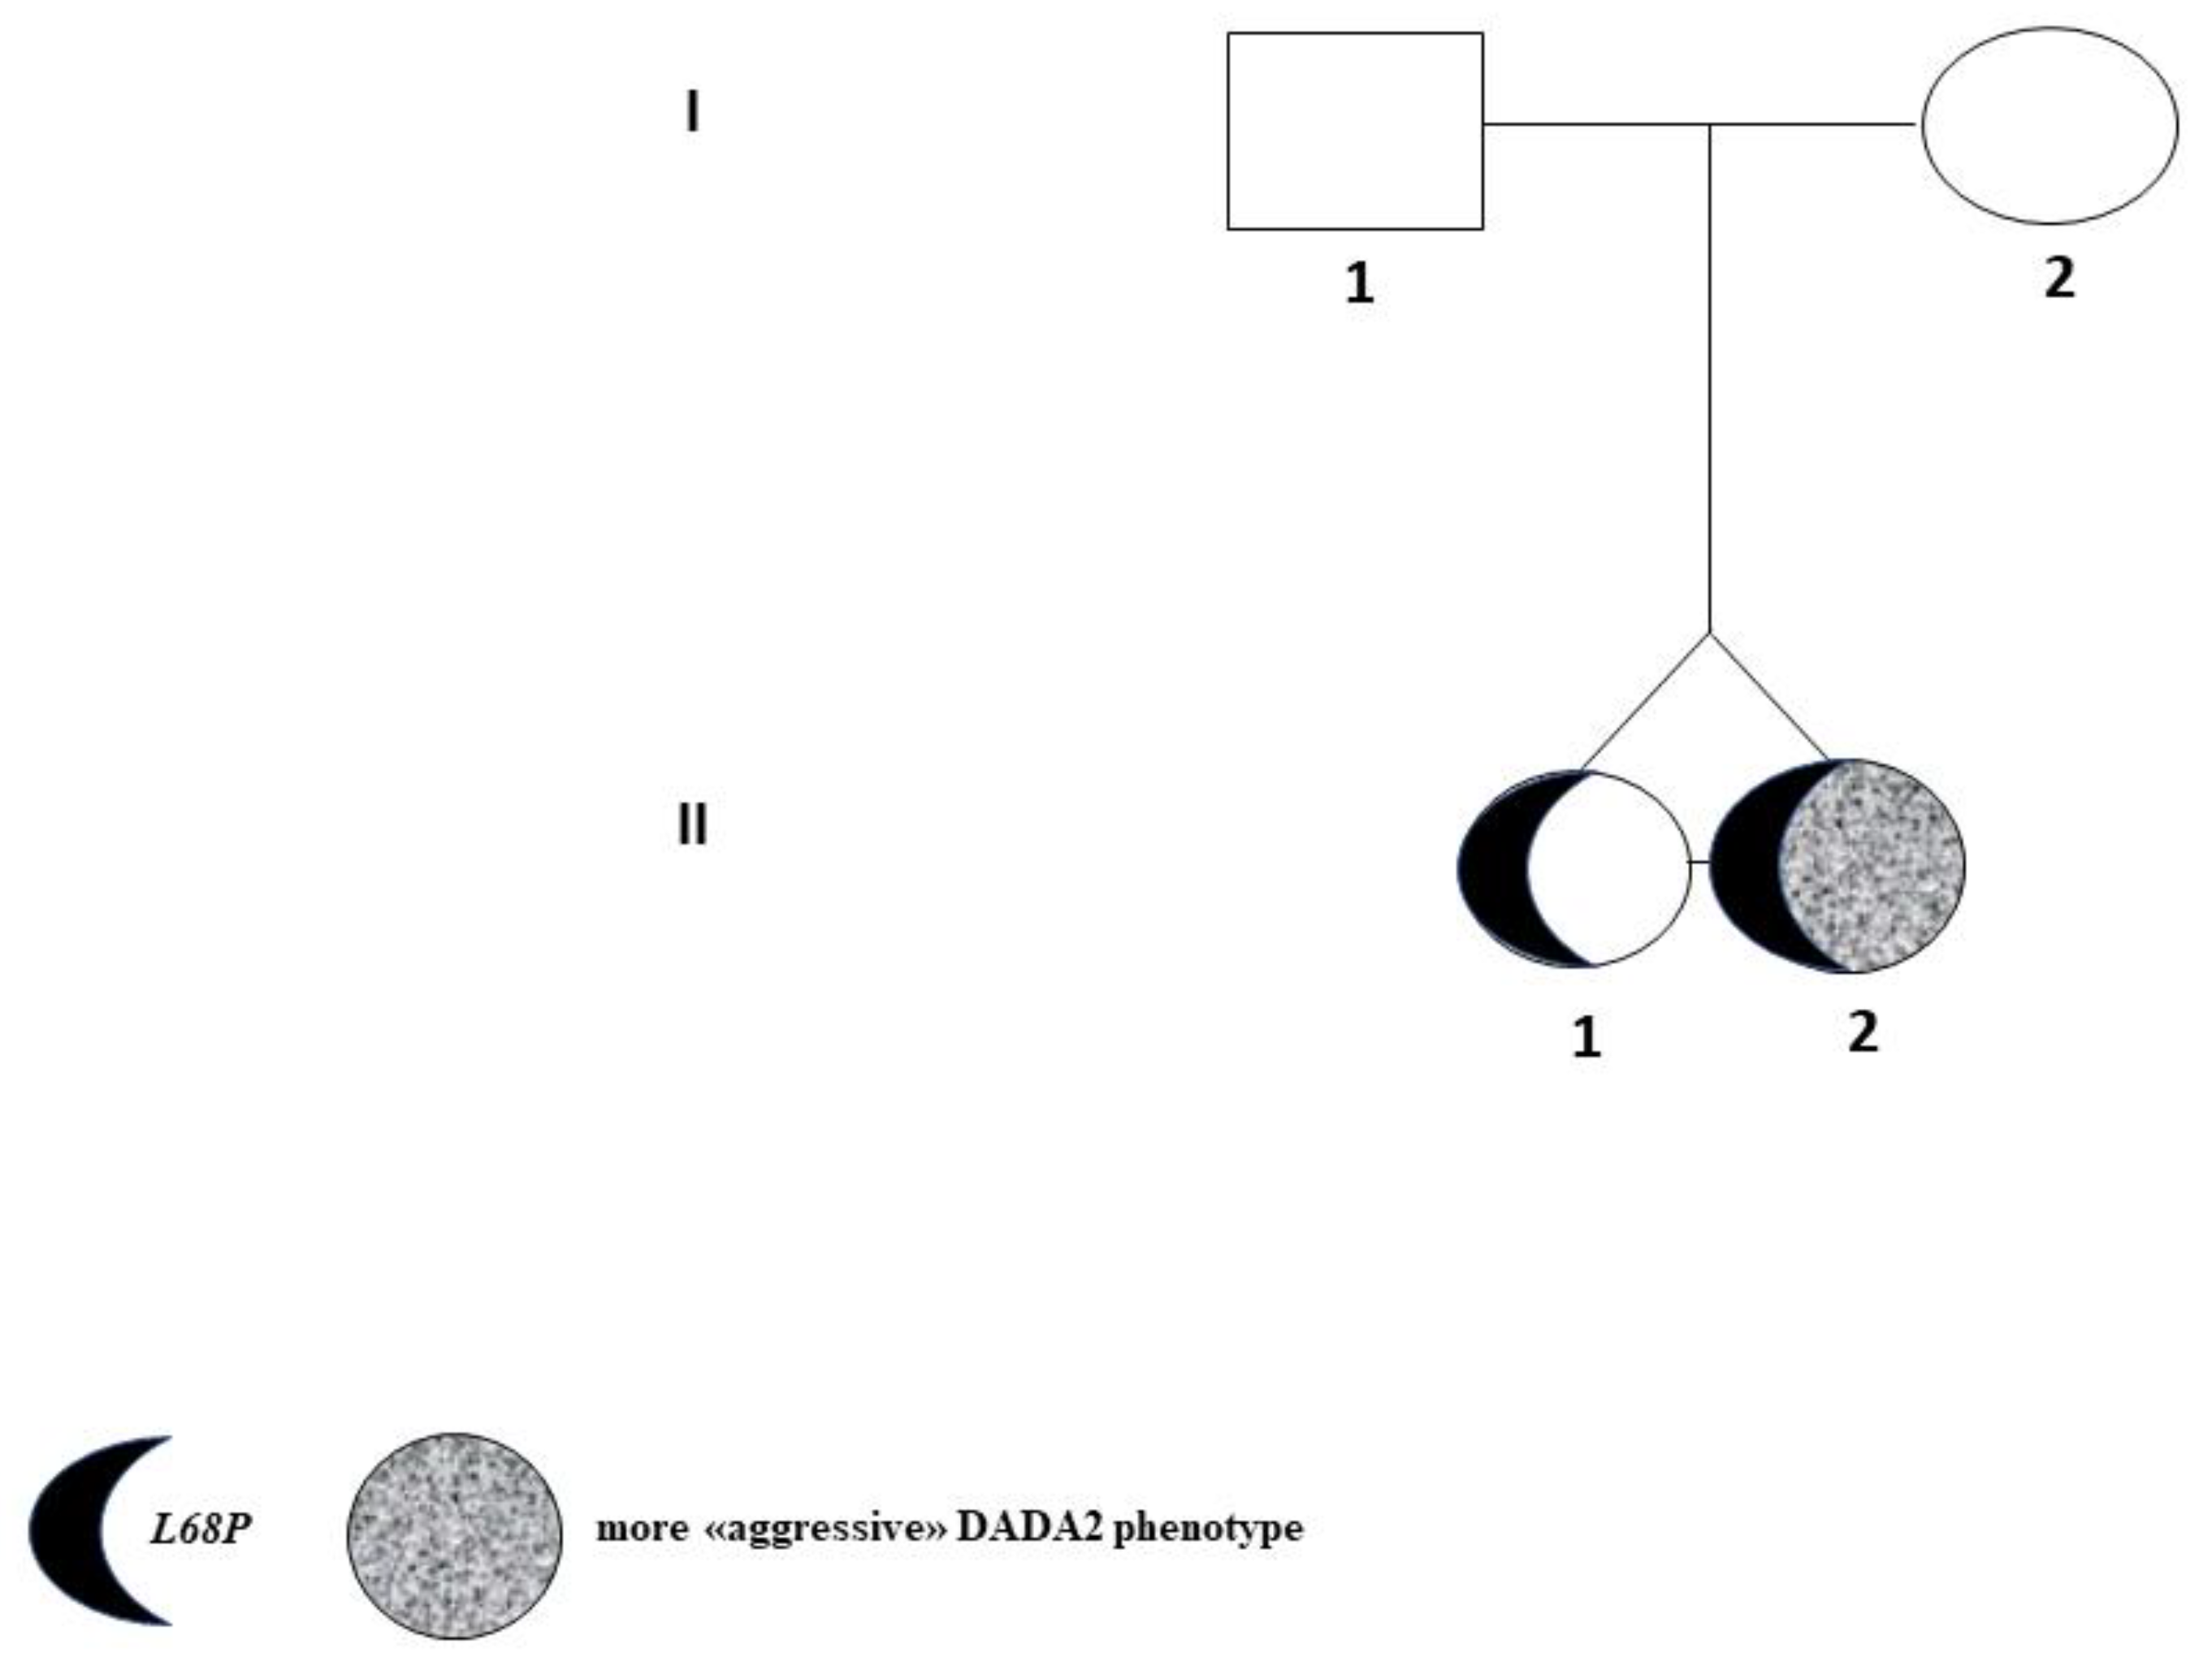

A Novel Germline Mutation of ADA2 Gene in Two “Discordant” Homozygous Female Twins Affected by Adenosine Deaminase 2 Deficiency: Description of the Bone-Related Phenotype

2. Case Reports

| (A) II-1 Tw1. |

| (B) II-2 Tw2. |